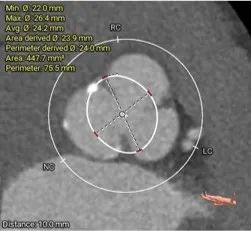

瓣上多平面分析

• 三叶式主动脉瓣,以风湿性改变为主,瓣叶显著增厚,R-L间纤维粘连,轻度钙化,钙化主要沿无冠窦瓣缘分布,LVOT直筒型对人工瓣膜的释放技巧有较高要求

• 左、右冠高度可,切线位测量,无冗长瓣叶,结合瓦氏窦、STJ 内径综合预估,冠脉阻塞风险适中

• 结合瓣环及瓣上分析数据,选择18mm球囊预扩,尽可能减小破坏瓣上结构,植入TaurusElite系统AV26瓣膜,视评估情况决定是否后扩。